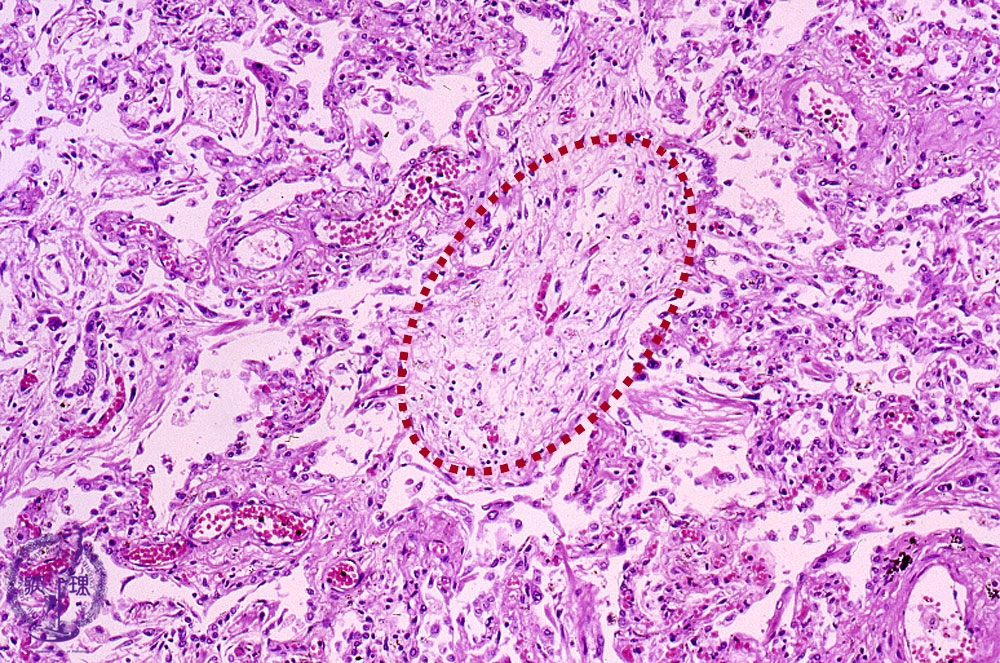

Microscopic view (HE stain, intermediate power view): Within the affected bronchiolar lumen, polypoid granulation tissue (Masson body, dotted line) is seen.